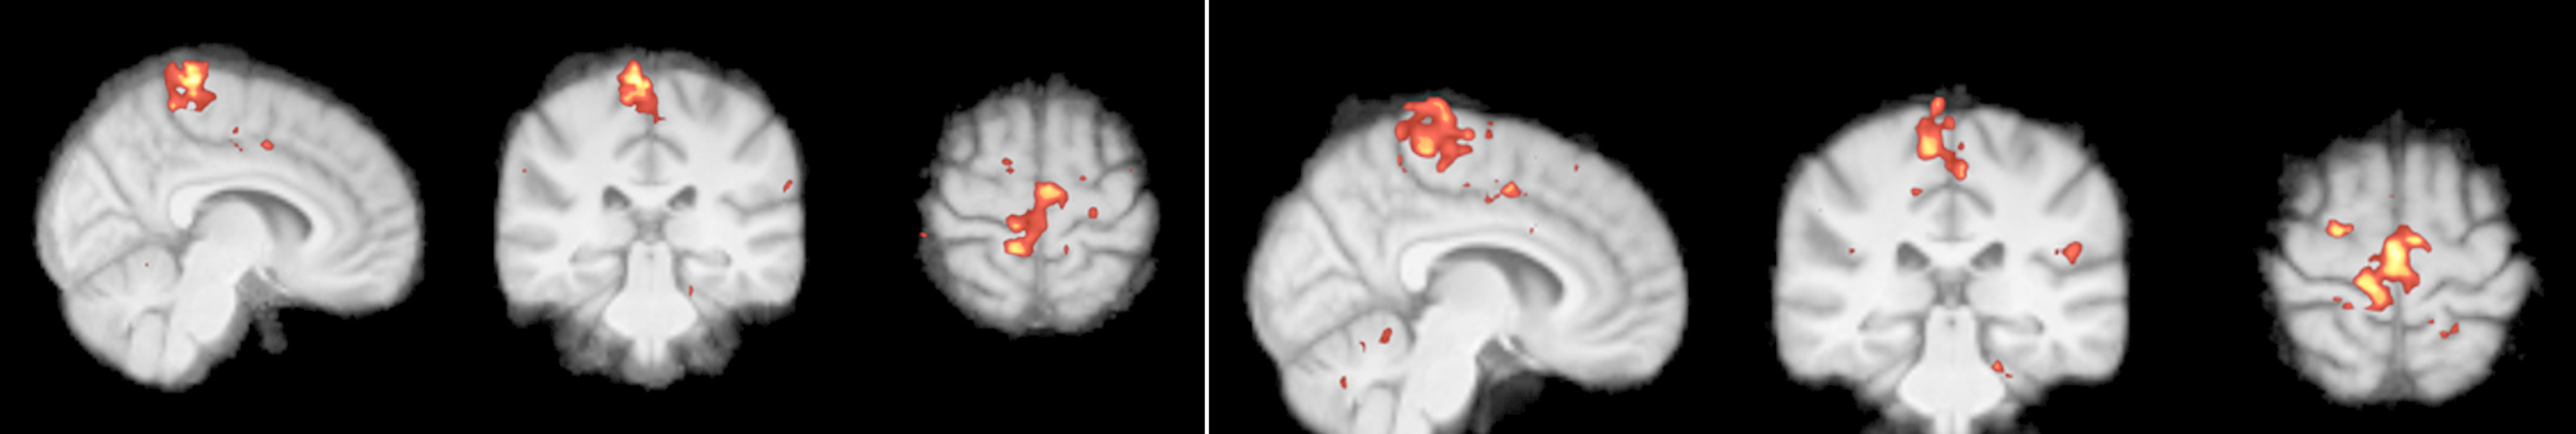

Funktionelle und metabolische MRT:

Es ist bekannt, dass chronische Schmerzen zu funktionellen und strukturellen Änderungen im Gehirn führen. In diesem Projekt untersuchen wir den Einfluss der Rückenmarksstimulation auf diesen Prozess.